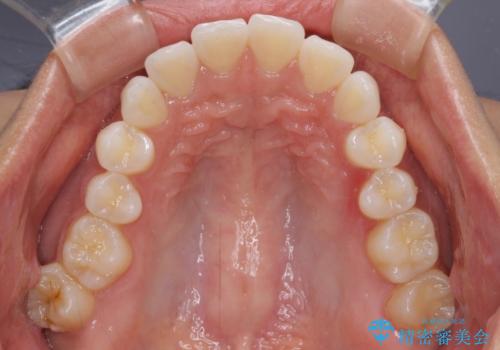

- 前に出ている上顎前歯が気になるとのことで来院された患者様です。

インビザラインを用い、IPR(歯と歯の間を削る)と歯列全体を後方に移動させることで、可能な限り前歯の突出感を改善することとしました。

元々の歯列も整っており、横顔の印象の出っ歯ではなかったため、仕上がりに満足できない可能性があると心配しておりましたが、口が閉じやすくなり、患者様には大変満足していただきました。